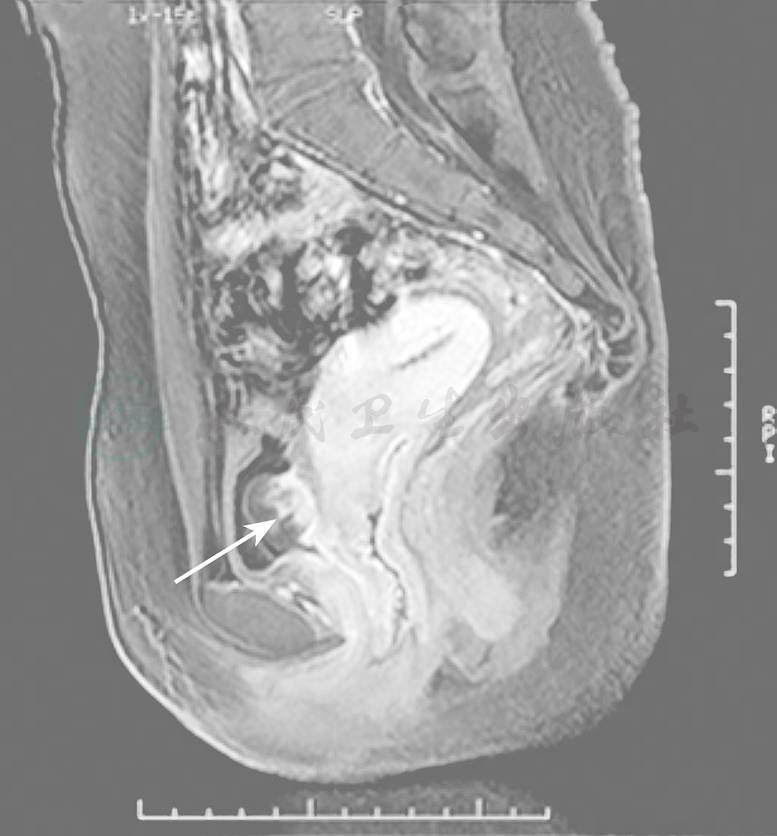

膀胱转移瘤的主要临床表现为血尿及下腹部不适,如凝血块堵塞尿道口,亦可引起排尿困难。在诊断上,除了通过影像学进行诊断(图1),还可以通过膀胱镜检查进一步明确诊断。虽然膀胱转移的诊断不困难,但还需和来自肾转移的血尿以及由某些化学药物如喜树碱、环磷酰胺等所致的血尿相区别。

图1膀胱转移的MRI影像